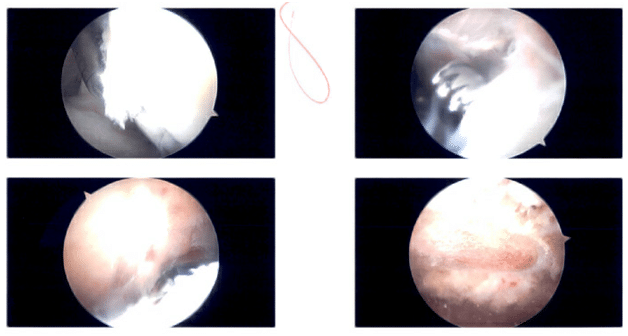

Intraoperative Shoulder Arthroscopic Images.

There was fraying of the acromion along with a curved configuration (Type 2 acromion). The acromion was cleaned using a thermal wand followed by an acromioplasty with a bur. The CA ligament was also released. After a thorough acromioplasty, the AC joint was examined and found to be degenerative. 1 cm of distal third clavicle excision was also performed using a wand and followed by a bur. Final pictures were taken. Now the rotator cuff tear was seen and cleaned. The footprint of the rotator cuff was prepared.

Accessory incisions were given for the lateral portal as well as posterosuperior portals for the insertion of the anchor. A Healicoil peak anchor was used. The two-tailed anchor was used and inserted into the head of the humerus. The tails were passed in a mattress suture pattern to the rotator cuff tear. The knots were tied.

The anterior knot was repaired at medial row only. The posterior knot was put in a double-row repair using a multi fix anchor. Final pictures were taken. The shoulder was thoroughly washed and drained. The closure was performed using #4-0 nylon. The dressing was done using Adaptic, 4×4, ABD, and tape. The right lower extremity was put into an abduction pillow shoulder immobilizer. The patient was extubated and moved to recovery in a stable condition.